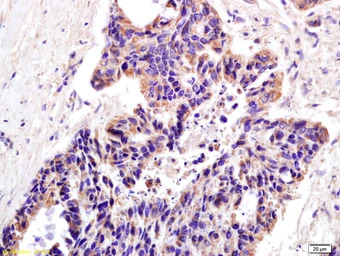

IHC-P analysis of human lung carcinoma tissue using GTX51780 XAGE2 antibody.

Dilution : 1:200